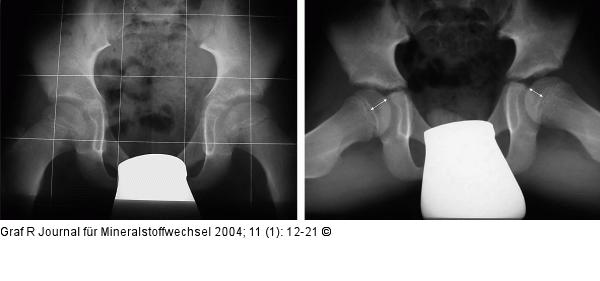

Abbildung 7: Hüftgelenk Frühstadium mit beginnendem Kondensationsstadium links. Sowohl auf der ap-, als auch auf der axialen Aufnahme ist die angedeutete Verminderung der Höhe der Kopfkalotte mit leichter Verdichtung der Strukturen erkennbar. |

Frühstadium mit beginnendem Kondensationsstadium links. Sowohl auf der ap-, als auch auf der axialen Aufnahme ist die angedeutete Verminderung der Höhe der Kopfkalotte mit leichter Verdichtung der Strukturen erkennbar. |